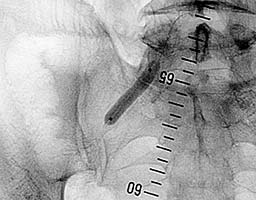

В место стеноза проведен баллон-катетер

диаметром 8мм, произведена троекратная дилятация по 1 мин (рис.2).

| Рис.2 |